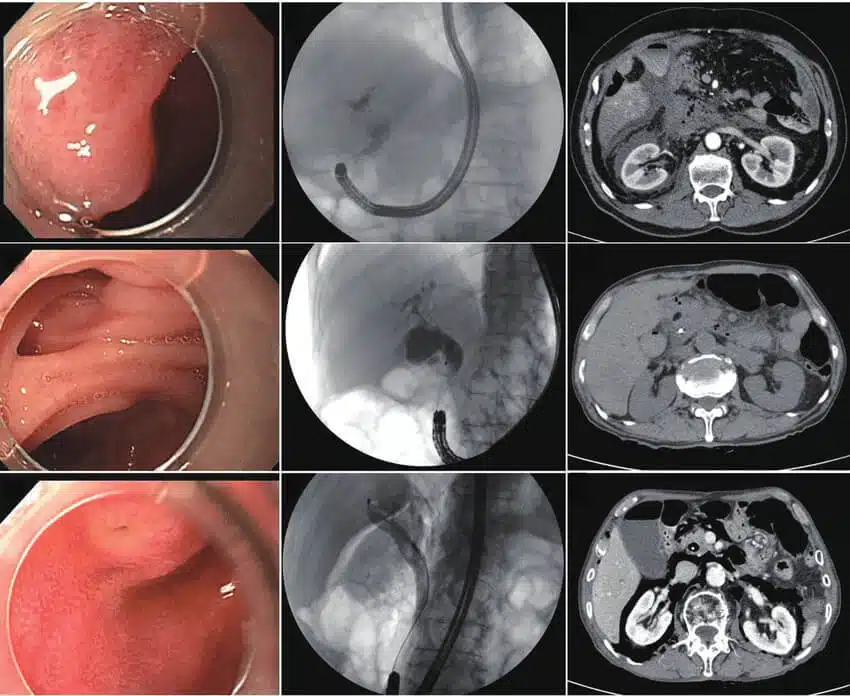

ERCP (endoscopic retrograde cholangiopancreatography) process, is a method to treat problems in the liver, bile ducts, gallbladder, and pancreas and also diagnose these problems. It connects information from X-ray and the use of an endoscope. Your doctor guides the scope over mouth and throat, then down the throat, stomach, and the first part of the small intestine. Mostly your healthcare provider could view other related organs and check for difficulties. Next, a tube is passed over the scope and inserts a dye. This shows the organs on X-ray separately.